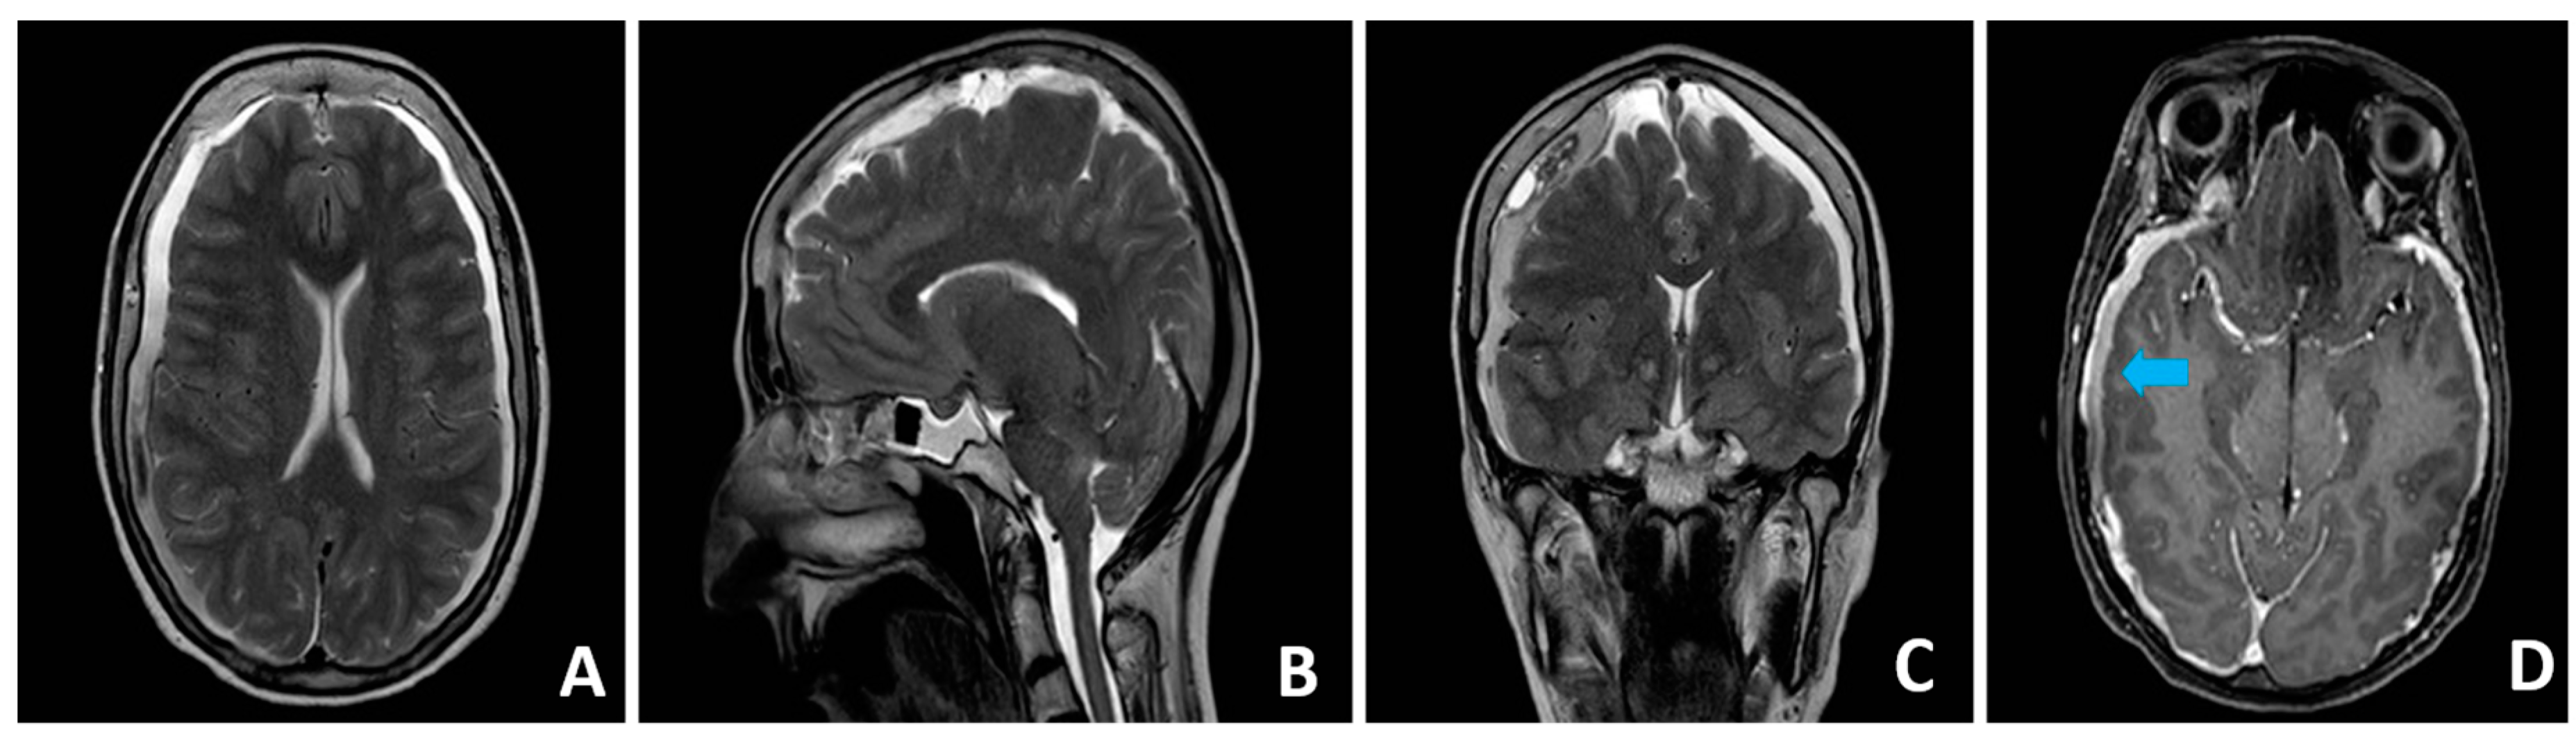

3.1. Case Presentation